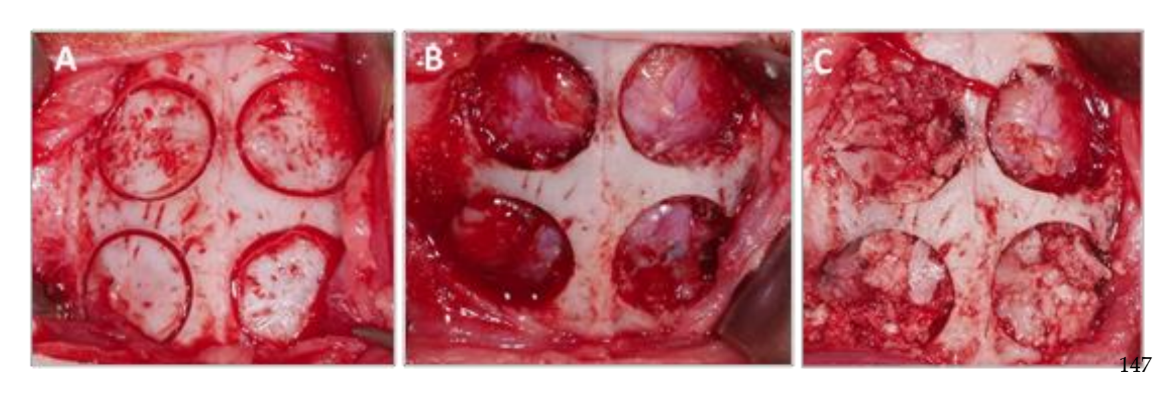

Quatro defeitos ósseos não autointegrantes foram realizados (diâmetro: 9 mm; profundidade: aproximadamente 3 mm, até atingir a dura-máter) no osso parietal, de cada lado da linha média do crânio, utilizando uma trefina (Helmut-Zepf Medical GmbH, Seitingen, Alemanha) montada em um micromotor cirúrgico a 2000 rpm sob irrigação com solução salina. Instrumentos piezoelétricos foram utilizados para remover a tabela interna e o osso medular de cada defeito. A profundidade foi controlada com uma sonda periodontal. Uma vez realizados os defeitos, o osso obtido foi moído e o material obtido foi dividido em duas partes iguais. A configuração dos grupos foi a seguinte: Grupo 1 (PSB): mistura de membrana de fibrina rica em plaquetas (P) + silício (S) + osso autólogo (B); Grupo 2 (PS): membrana de fibrina rica em plaquetas (P) + silício (S); Grupo 3 (SB): silício (S) + osso autólogo (B) e por último o Grupo 4 (CONTROLE) no qual nenhum material regenerativo foi colocado. A distribuição dos grupos no osso parietal pode ser vista na Tabela 1.

Após a sutura, agentes anti-inflamatórios e analgésicos foram administrados (carprofeno 1 ml / 12,5 kg e buprenorfina 0,05 mg / kg). Finalmente, os animais foram sacrificados usando uma overdose intravenosa de cloreto de potássio após 3 semanas. O procedimento cirúrgico pode ser visto na Figura 1.